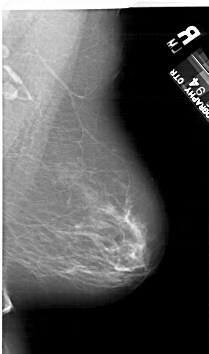

A_1124_1.LEFT_MLO

LEFT_MLO LINES 6196 PIXELS_PER_LINE 3616 BITS_PER_PIXEL 12 RESOLUTION 43.5 OVERLAY